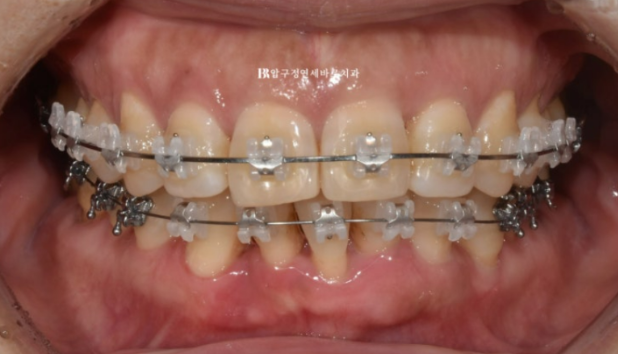

23.03

가장 상태가 안 좋은 아래 앞니 1개를 먼저 발치하고 클리피씨 장치로 나머지 치아를 배열합니다.

순차적으로 발치하는 이유는 처음부터 2개를 한 번에 빼면 빈공간이 너무 크기 때문입니다.

23.10

위에는 교정용 나사를 초반부터 심고 사랑니 공간으로 전체 치아를 뒤로 밀면서 돌출 해소를 하는 중입니다.